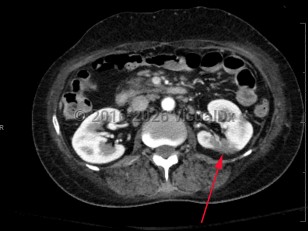

Renal calculus

Renal infarctionRenal infarction

Perinephric abscessPerinephric abscess

Ureteral calculus